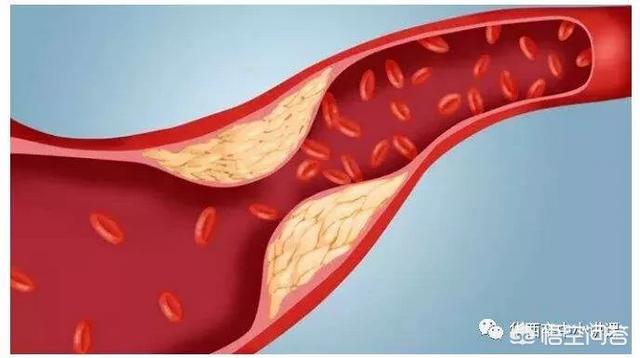

血管狭窄を引き起こし、最も深刻なプラークは、心血管プラーク、または頸動脈プラークであり、これらのプラークの悪化は、心筋虚血、脳虚血につながる;積極的に制御しない場合、あるいはプラークの血栓症の破裂が発生し、心筋梗塞、脳梗塞をもたらす。

高脂血症などの心血管危険因子の影響により、血管の内壁は徐々に傷つき、血液中の余分な脂質は徐々に血管壁の下に沈着し、黄色い粥腫性脂質コアを形成し、最終的には脂質コアに線維性被膜が形成され、これが動脈プラークの形成過程である。 プラークは動脈硬化を引き起こす危険因子であり、安定性や破裂に問題のあるプラークは、反応性血小板血小板の反応性凝集は血栓を形成し、動脈血管を閉塞させ、梗塞性心血管病を引き起こすことさえある。したがって、私たちはプラークの問題に注意を払う必要がありますが、通常、すでに形成されたプラークを元に戻したり除去したりすることは非常に困難であり、私たちがしなければならないことは、合理的な薬物療法と運動によってプラークの形成を予防し、既存のプラークに対して、プラークの安定性を維持するように努め、動脈硬化のプロセスを遅らせ、プラークの破裂がより大きなリスクを引き起こすのを防ぐことです。

プラークは、静脈プラーク、動脈プラークを持って、それは複数の病因因子の役割にある、沈殿物の脂質化のために、単刀直入に言えば、つまり、あなたがより多くのグリース、消化と使用することはできません、血中脂質4と他の多因子の影響下で、内膜に損傷を与え、血管の内層に沈着し、黄色のアテローム性脂質のコアの形成、および最終的に線維性キャップが持続的な炎症にさらされている場合、通常は非常に安定している脂質のコア、上の線維性コアの形成にある攻撃は、飲酒、怒り、夜更かし、少ない水を飲むなど、線維性キャップが破裂し、プラークが流出し、血液中の血小板が結婚フラッシュ、血栓と呼ばれるトラブルメーカーの子供を出産し、この子は、血管をブロックするために悪いことをすることに特化し、トラブルを作るためにさまよう、血管の内腔に血栓が同時に狭くなるだけでなく、破裂、急性心脳血管イベント、脳卒中、心筋梗塞、肺塞栓症、腎不全、静脈瘤などを誘発する。などである。したがって、プラークを除去することは、血管の詰まりを取り除くだけでなく、急性心血管系および脳血管系イベントを予防することにもなり、誰もが関心を寄せている。

動脈プラークは、複数の病因因子の影響下にある動脈内膜の損傷によって引き起こされる一連の炎症反応であり、後に二次的なアテローム性プラークが生成される。プラークの形成は人体にとってより有害であり、同時に血管の内腔を狭くし、破裂して急性心血管系イベントを誘発することもある。したがって、プラークを除去することは血管の詰まりを解消するだけでなく、急性心血管系イベントを予防することにもなり、これはすべての患者の心臓の鼓動である。プラークの治療には、血中脂質、血圧、血糖値などのコントロール、減塩、低コレステロール食、運動量の増加、禁煙、アルコール制限などの悪い生活習慣の改善など、病気の原因から始めるか、上記の治療の上に薬物療法を行うことができます。薬の選択は、アトルバスタチン、レセルプルバスタチンなどのスタチン系薬剤がアテローム性プラークの治療によく使用されます。具体的な治療計画は専門医の指導のもとに立てるべきである。

アテローム性動脈硬化症は、成人であれば思春期から誰もが経験する動脈血管の内皮病変である。数十年かけてゆっくりと進行し、最終的にはアテローム性動脈硬化斑を形成して血管を詰まらせたり、破裂させたりして、脳出血、脳梗塞、冠動脈疾患、大動脈瘤の分離などの重篤な心血管・脳血管疾患を引き起こす。

プラークが発生する過程にはいくつかの段階があり、まず血管の内皮が傷つき、血管内面の保護層が「壊れる」ようになると、血液中の高分子脂肪が低比重リポ蛋白と呼ばれる一種の物質によって血管壁の内膜中膜層に大量に運ばれて蓄積し、血管壁が肥厚し、医療では内膜中膜層が1mm以上になると動脈硬化が起こっていると言われています。内膜中膜層の肥厚が1mmを超えると、局所的に凝集して塊になったような動脈硬化、すなわち初期プラークが生じたといわれる。